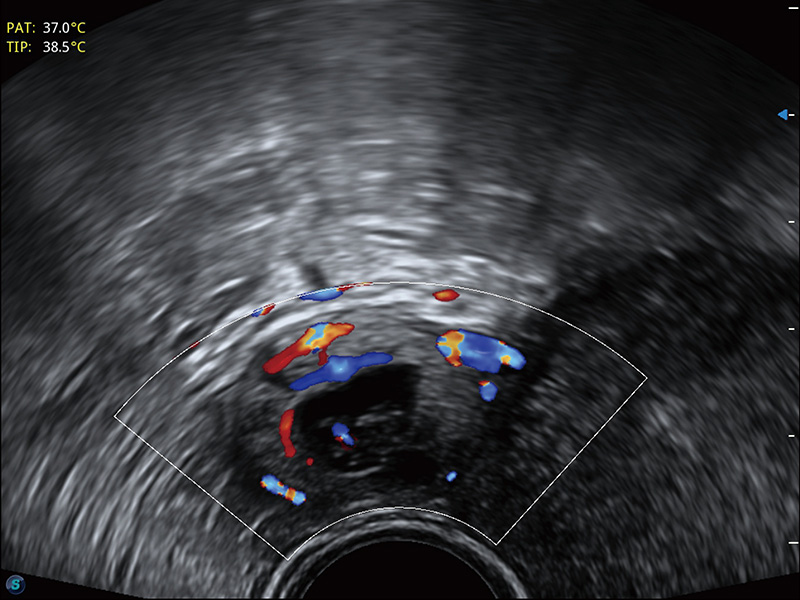

宫外孕血流